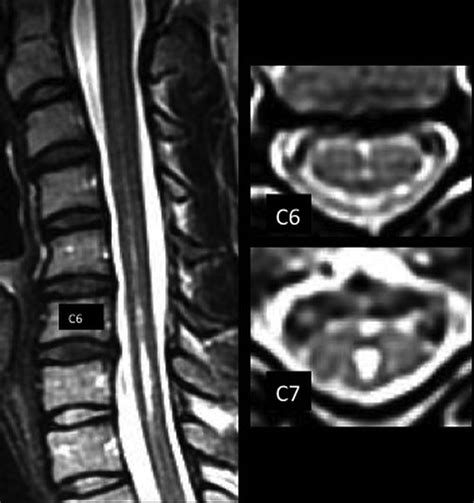

• Diagnostic Imaging: Magnetic resonance imaging (MRI) and computed tomography (CT) scans can be used to visualize the anterior fissure and assess its integrity. These imaging techniques are essential for diagnosing spinal cord injuries and neurological disorders.

• Imaging Techniques: MRI and CT scans are essential for visualizing the spinal cord and the anterior fissure. These imaging techniques can help identify structural abnormalities, such as tumors or fractures, and assess the integrity of the anterior spinal artery.